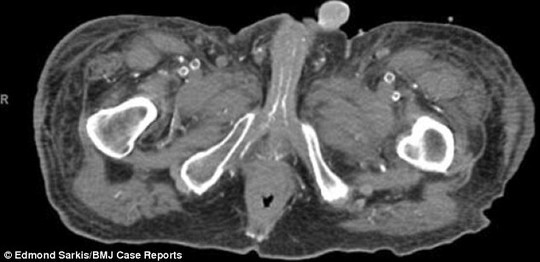

Động mạch bị vôi hóa trong "của quý" và xương chậu người đàn ông

Tiến sĩ Sarkis cho biết ban đầu, các bác sĩ chẩn đoán nam bệnh nhân bị calciphylaxis – một hội chứng nghiêm trọng khiến canxi tích tụ trong các mạch máu nhỏ ở các mô mỡ và da. Bệnh thận và việc dùng thuốc làm loãng máu cũng khiến căn bệnh nặng thêm. Khi bị bệnh thận, cơ quan này ngừng lọc chất độc ra khỏi máu khiến canxi bị tích tụ trong động mạch làm mạch máu tắt nghẽn, sinh cục máu đông dẫn đến hoại tử gây đau đớn.